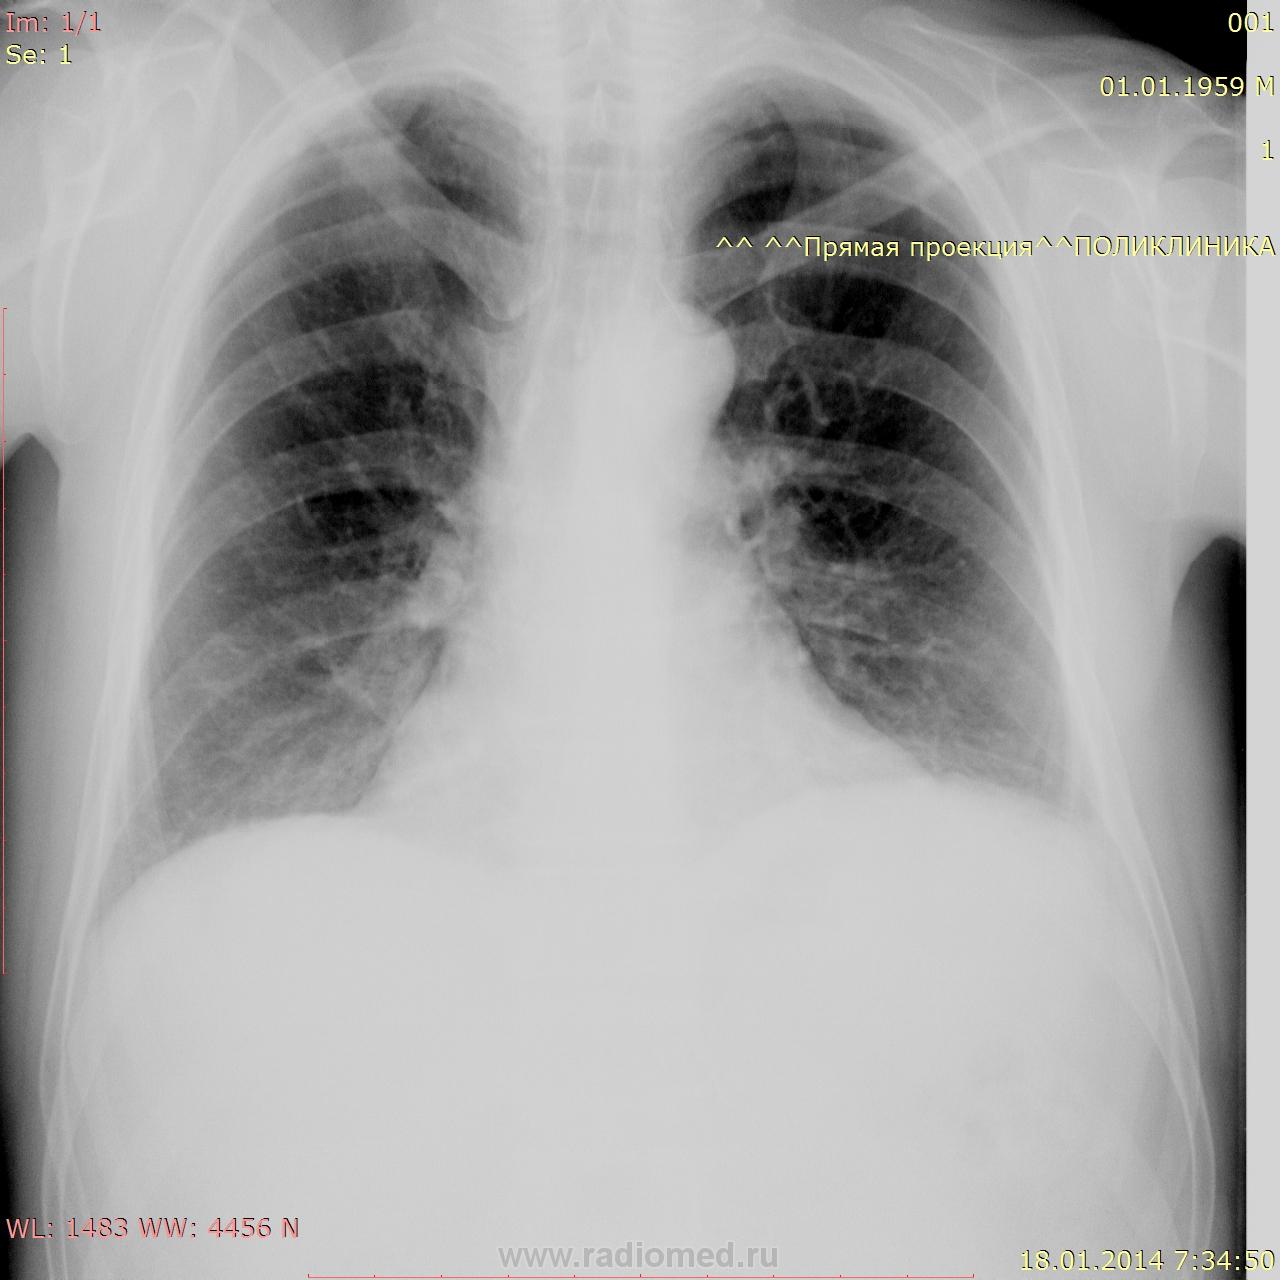

Пока кабинет закрыт на ремонт, снимаю ОГК на передвижке. Что посоветуете, коллеги?

В принцине, ничего особенного. А на чем глаз остановился?

Добрый день, Андрей Юрьевич. Смутило положение средостения и куполов диафрагмы, Просил правый бок сделать. Теперь "мерещится" инфильтрация S2. Могу Dicom скинуть.

Вот ваш пример. Левый купол стоит несколько выше правого, это может быть при поражении диафрагмально нерва метастатически увеличенными лимфоузлам средостения. Что Вам делать? Дообследовать своими силами вы не можете. Варианта два: 1. написать "Возр. изменения", и ждать , во что это выльется; 2. Написать "Нельзя исключить мтс в л/у средостение. Рек. КТ". Выбор за Вами.

Дорофей! Я бы сначала попробовала переделать на полном вдохе,

Вроде как,ничего криминального.